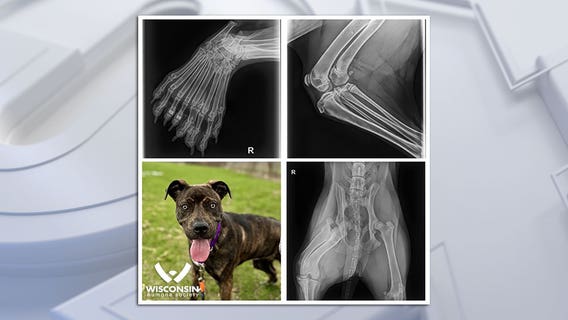

Wisconsin Humane Society: 5-legged dog to be up for adoption in Kenosha

The Wisconsin Humane Society is sharing the story of the first five-legged dog they've seen in the organization's 145-year history.

5-legged dog adopted from Wisconsin Humane Society in Kenosha

It's a story that ends on a paws-itive note! Bella, the 5-legged dog at the Wisconsin Humane Society, was officially adopted on Friday, May 3.